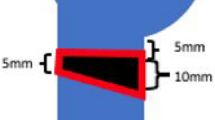

An unstable three-part fracture of the humeral head was simulated by an osteotomy of the greater tuberosity laterally to the sulcus intertubercularis and a V-shaped osteotomy at the anatomical neck. Prior to the osteotomy, the fracture lines were marked on the specimen. The first osteotomy was positioned at the level of the cartilage-bone border rectangularly to the shaft axis. The second osteotomy was angulated to create a wedge-shaped fracture gap with a height of 10 mm on the medial side. (Fig. 1). The osteotomy was performed using an oscillating saw.